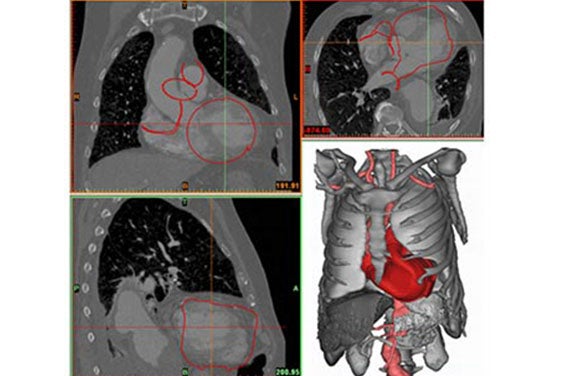

Fritschi et al. selected medical images from 27 patients as the input for their design validation. They segmented these datasets to create detailed virtual models in Mimics. With the help of the software, all 3D models were aligned using a common coordinate system to derive meaningful measurements from the virtual analysis (Figure 1).

Figure 1 and Figure 2

Fritschi et al. ensured the reproducibility of the model creation by using tools that can be applied globally to the images, such as thresholding, region growing, and morphological operations (Figure 2). The authors were interested in determining the spatial constraints of the pericardial cavity and the valve position and orientation. They used Mimics to measure oblique parameters according to anatomical landmarks (Figure 1). All measurements made were comparable between patients.